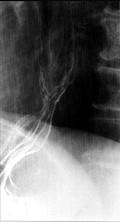

问题 女性,65岁,进行性吞咽困难半年,消瘦,钡餐检查如图,最佳的诊断是()

选项 A.贲门失弛缓症 B.食道静脉曲张 C.食管鳞状(上皮)细胞癌 D.贲门癌 E.返流性食道炎

答案 C